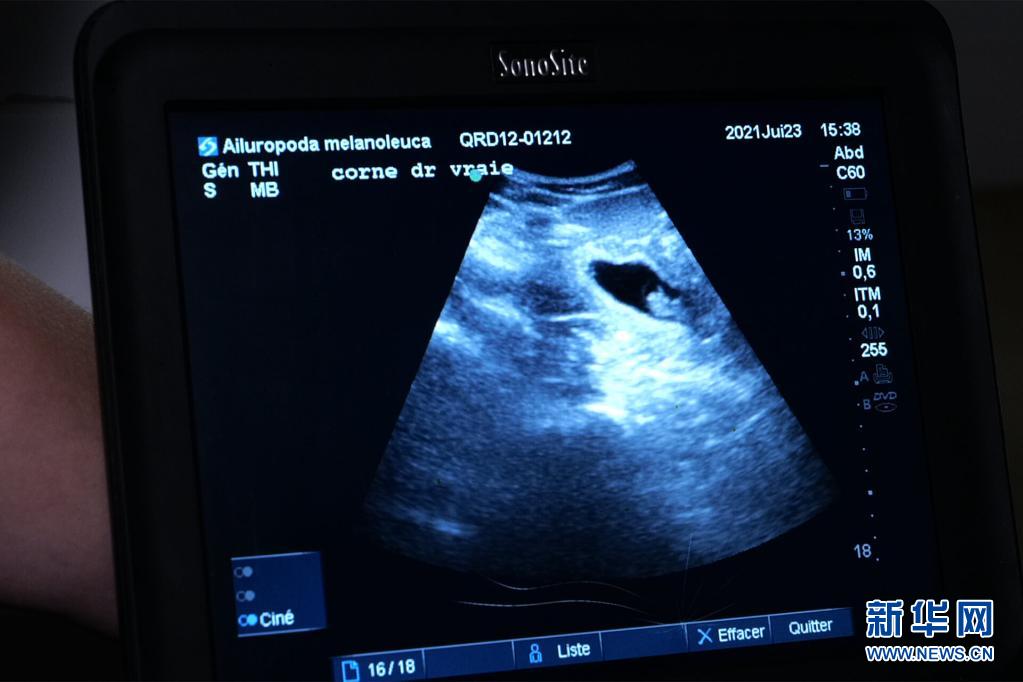

这是7月23日在法国中部圣艾尼昂市博瓦勒野生动物园拍摄的大熊猫“欢欢”的超声波检查照片。新华社发(博瓦勒野生动物园供图)

博瓦勒野生动物园当天发表新闻公报说,继20日发现“欢欢”腹中首个胚胎后,动物园兽医23日在为“欢欢”做超声波检查时,在其子宫另一侧发现第二个胚胎。